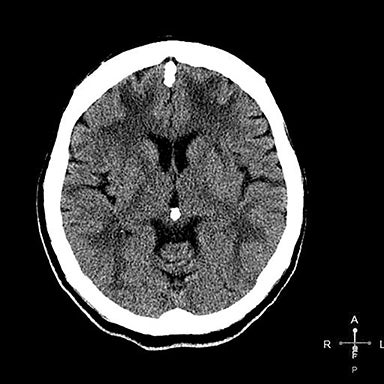

Компьютерная томография при токсической энцефалопатии выявляет следующие анатомические признаки:

В нативном режиме возможны участки пониженной плотности в белом веществе мозга, чаще симметрично в лобно-теменных долях и в области мозолистого тела.

В режиме сканирования мягких тканей визуализируются признаки корковой и подкорковой атрофии, если токсическое воздействие носит хронический характер.

В ряде случаев при остром токсическом поражении выявляется генерализованный отёк мозга с потерей дифференциации коры и белого вещества.

- Объём и локализация участков сниженной плотности определяются с высокой точностью, особенно в условиях неотложной диагностики.

- Протяжённость поражения симметричных структур мозга позволяет предположить системное метаболическое или токсическое воздействие.

- Выраженность корковой атрофии и расширения желудочков оцениваются при хроническом течении энцефалопатии.